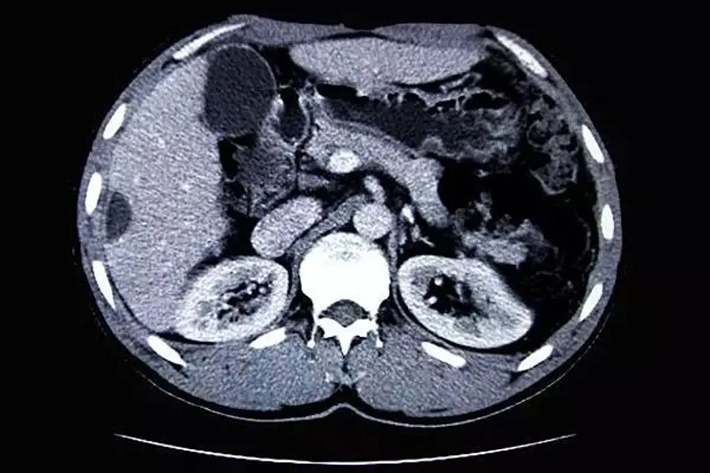

CT es la abreviatura de Computed Tomography en inglés, y su traducción significa tomografía computarizada. El principal medio de inspección utilizado es la radiografía, a través del escaneo penetrante del cuerpo por rayos X, y la imagen de la parte escaneada se obtiene a través de un detector altamente sensible, que tiene las características de escaneo rápido e imagen clara.

El poder de penetración de rayos X es muy fuerte. Al penetrar en el cuerpo humano, formará diferentes tasas de absorción según los diferentes tejidos y las diferentes densidades del cuerpo humano, dejando imágenes en blanco y negro con diferentes escalas de grises en la película fotosensible. Los médicos pueden observar y analizar estas imágenes para conocer el estado de los tejidos internos del cuerpo humano y así hacer un diagnóstico de la enfermedad.

La TC se desarrolla sobre la base de la perspectiva de rayos X. La tomografía computarizada utiliza un dispositivo giratorio para realizar una exploración tomográfica del cuerpo humano, como cortar rodajas de zanahoria. El detector de alta sensibilidad recibe los rayos penetrantes a través del dispositivo giratorio y obtendrá Los datos se ingresan a la computadora y la imagen se reconstruye después de ser decodificada por la computadora.

La estructura principal del equipo de TC tiene tres partes, a saber: la parte de exploración, que se compone de tubos de rayos X, detectores y marcos de exploración; el sistema informático, que almacena y calcula la información y los datos recopilados mediante el escaneo; el sistema de visualización y almacenamiento de imágenes, que Las imágenes procesadas y reconstruidas se muestran en la pantalla del televisor o se toman con varias cámaras o cámaras láser para que las observen los médicos.

El equipo actual de TC se ha actualizado desde la primera generación hasta la quinta generación. Desde el principio, el área de escaneo es pequeña, el tiempo de escaneo es largo (varios segundos), los detectores son pocos (solo uno o dos) y la resolución es muy baja. Hasta ahora, el área de escaneo se ha expandido mucho, la resolución espacial puede alcanzar los 0,4 mm (milímetros), el tiempo de escaneo se reduce a 40 ms (milisegundos) y solo se necesitan 330 ms para escanear 64 capas de imágenes.

El método de escaneo solo se puede traducir desde el principio, y ahora puede realizar escaneo simple, escaneo mejorado y escaneo de contraste, y también puede realizar imágenes dinámicas tridimensionales.

tomografía computarizada

Se pueden ver los detalles de la lesión, la precisión es alta y los resultados del diagnóstico son más seguros. Es la primera opción para el diagnóstico de enfermedades en la cabeza, tórax, corazón, huesos, extremidades, etc.; pero algunos huesos tienen más artefactos, que afectan la visualización de las estructuras de tejido blando circundantes, como la base del cráneo y el canal espinal, etc., y se ven afectados por el movimiento respiratorio, es fácil pasar por alto lesiones pequeñas, como lesiones pequeñas en los pulmones y el hígado.

Además, los rayos X son rayos de alta energía que son dañinos para el cuerpo humano, por lo que las inspecciones frecuentes o prolongadas no son adecuadas. Algunos pacientes con enfermedades graves, como insuficiencia hepática y renal severa, hipertiroidismo, asma y ciertas lesiones alérgicas, no son aptos para este tipo de inspección. .